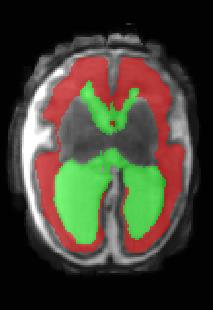

Limiting failures of machine learning systems is of paramount importance for safety-critical applications. In order to improve the robustness of machine learning systems, Distributionally Robust Optimization (DRO) has been proposed as a generalization of Empirical Risk Minimization (ERM). However, its use in deep learning has been severely restricted due to the relative inefficiency of the optimizers available for DRO in comparison to the wide-spread variants of Stochastic Gradient Descent (SGD) optimizers for ERM. We propose SGD with hardness weighted sampling, a principled and efficient optimization method for DRO in machine learning that is particularly suited in the context of deep learning. Similar to a hard example mining strategy in practice, the proposed algorithm is straightforward to implement and computationally as efficient as SGD-based optimizers used for deep learning, requiring minimal overhead computation. In contrast to typical ad hoc hard mining approaches, we prove the convergence of our DRO algorithm for over-parameterized deep learning networks with ReLU activation and a finite number of layers and parameters. Our experiments on fetal brain 3D MRI segmentation and brain tumor segmentation in MRI demonstrate the feasibility and the usefulness of our approach. Using our hardness weighted sampling for training a state-of-the-art deep learning pipeline leads to improved robustness to anatomical variabilities in automatic fetal brain 3D MRI segmentation using deep learning and to improved robustness to the image protocol variations in brain tumor segmentation. Our code is available at https://github.com/LucasFidon/HardnessWeightedSampler.